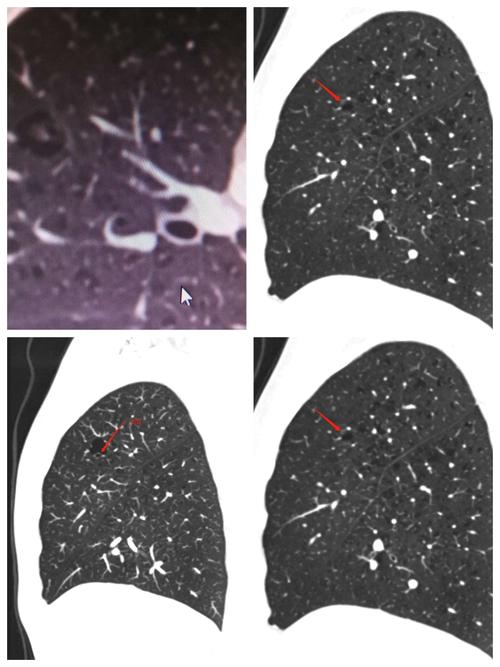

警惕易被误诊为肺大泡的囊腔型癌